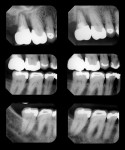

Patient History and Chief Complaint: A 53-year-old woman presented with a chief complaint of low-grade pain in the maxillary right quadrant for a 4-month duration. Radiographic and clinical analysis established a combined periodontal/endodontic lesion associated with tooth No. 2 as the pain source (Figure 1). The patient was previously diagnosed with periodontal disease and placed on a 4-month recare schedule, but her visits were intermittent.

Periodontal: Periodontal pocket depths measured 2 mm to 3 mm in the anterior sextants, and 2 mm to 5 mm in the posterior. Radiographically, generalized mild to moderate horizontal bone loss of between 1 mm and 3 mm was visible. Tooth No. 2, the source of the chief complaint, exhibited circumferential bone loss, with probing depths of 6 mm to 9 mm, secondary occlusal traumatism, and a suspected vertical root fracture. A periodontal diagnosis of AAP type III was made. Recession and abrasion were present on most of her maxillary teeth and the posterior mandibular teeth. This likely resulted from an aggressive toothbrush habit and predisposing anatomy.1 Apical root resorption was noted on tooth Nos. 7 through 9, 11, 23, 24, and 26 (Figure 6).